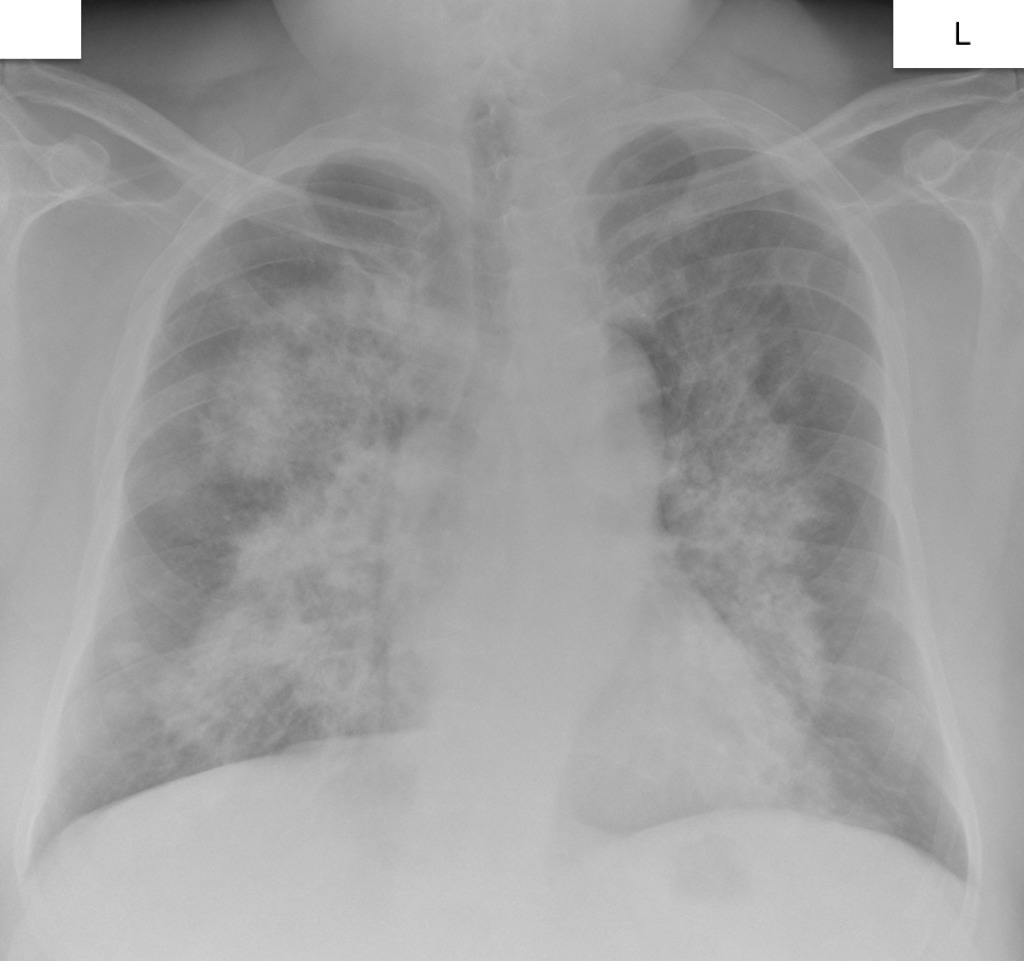

HOMEM, 50 ANOS, INTERNADO POR DISPNEIA + HEMOPTISE DE INÍCIO SÚBITO

áreas de opacidade em vidro fosco associadas a espessamento de septos interlobulares e intralobulares

HEMORRAGIA PULMONAR